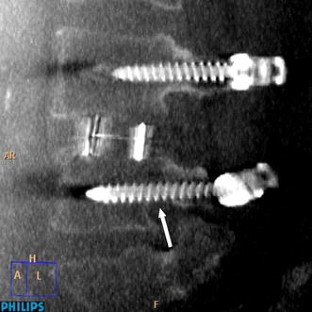

Fig. 1

Fig. 2

Fig. 3

Fig. 4

Fig. 5

Fig. 6

Fig. 7